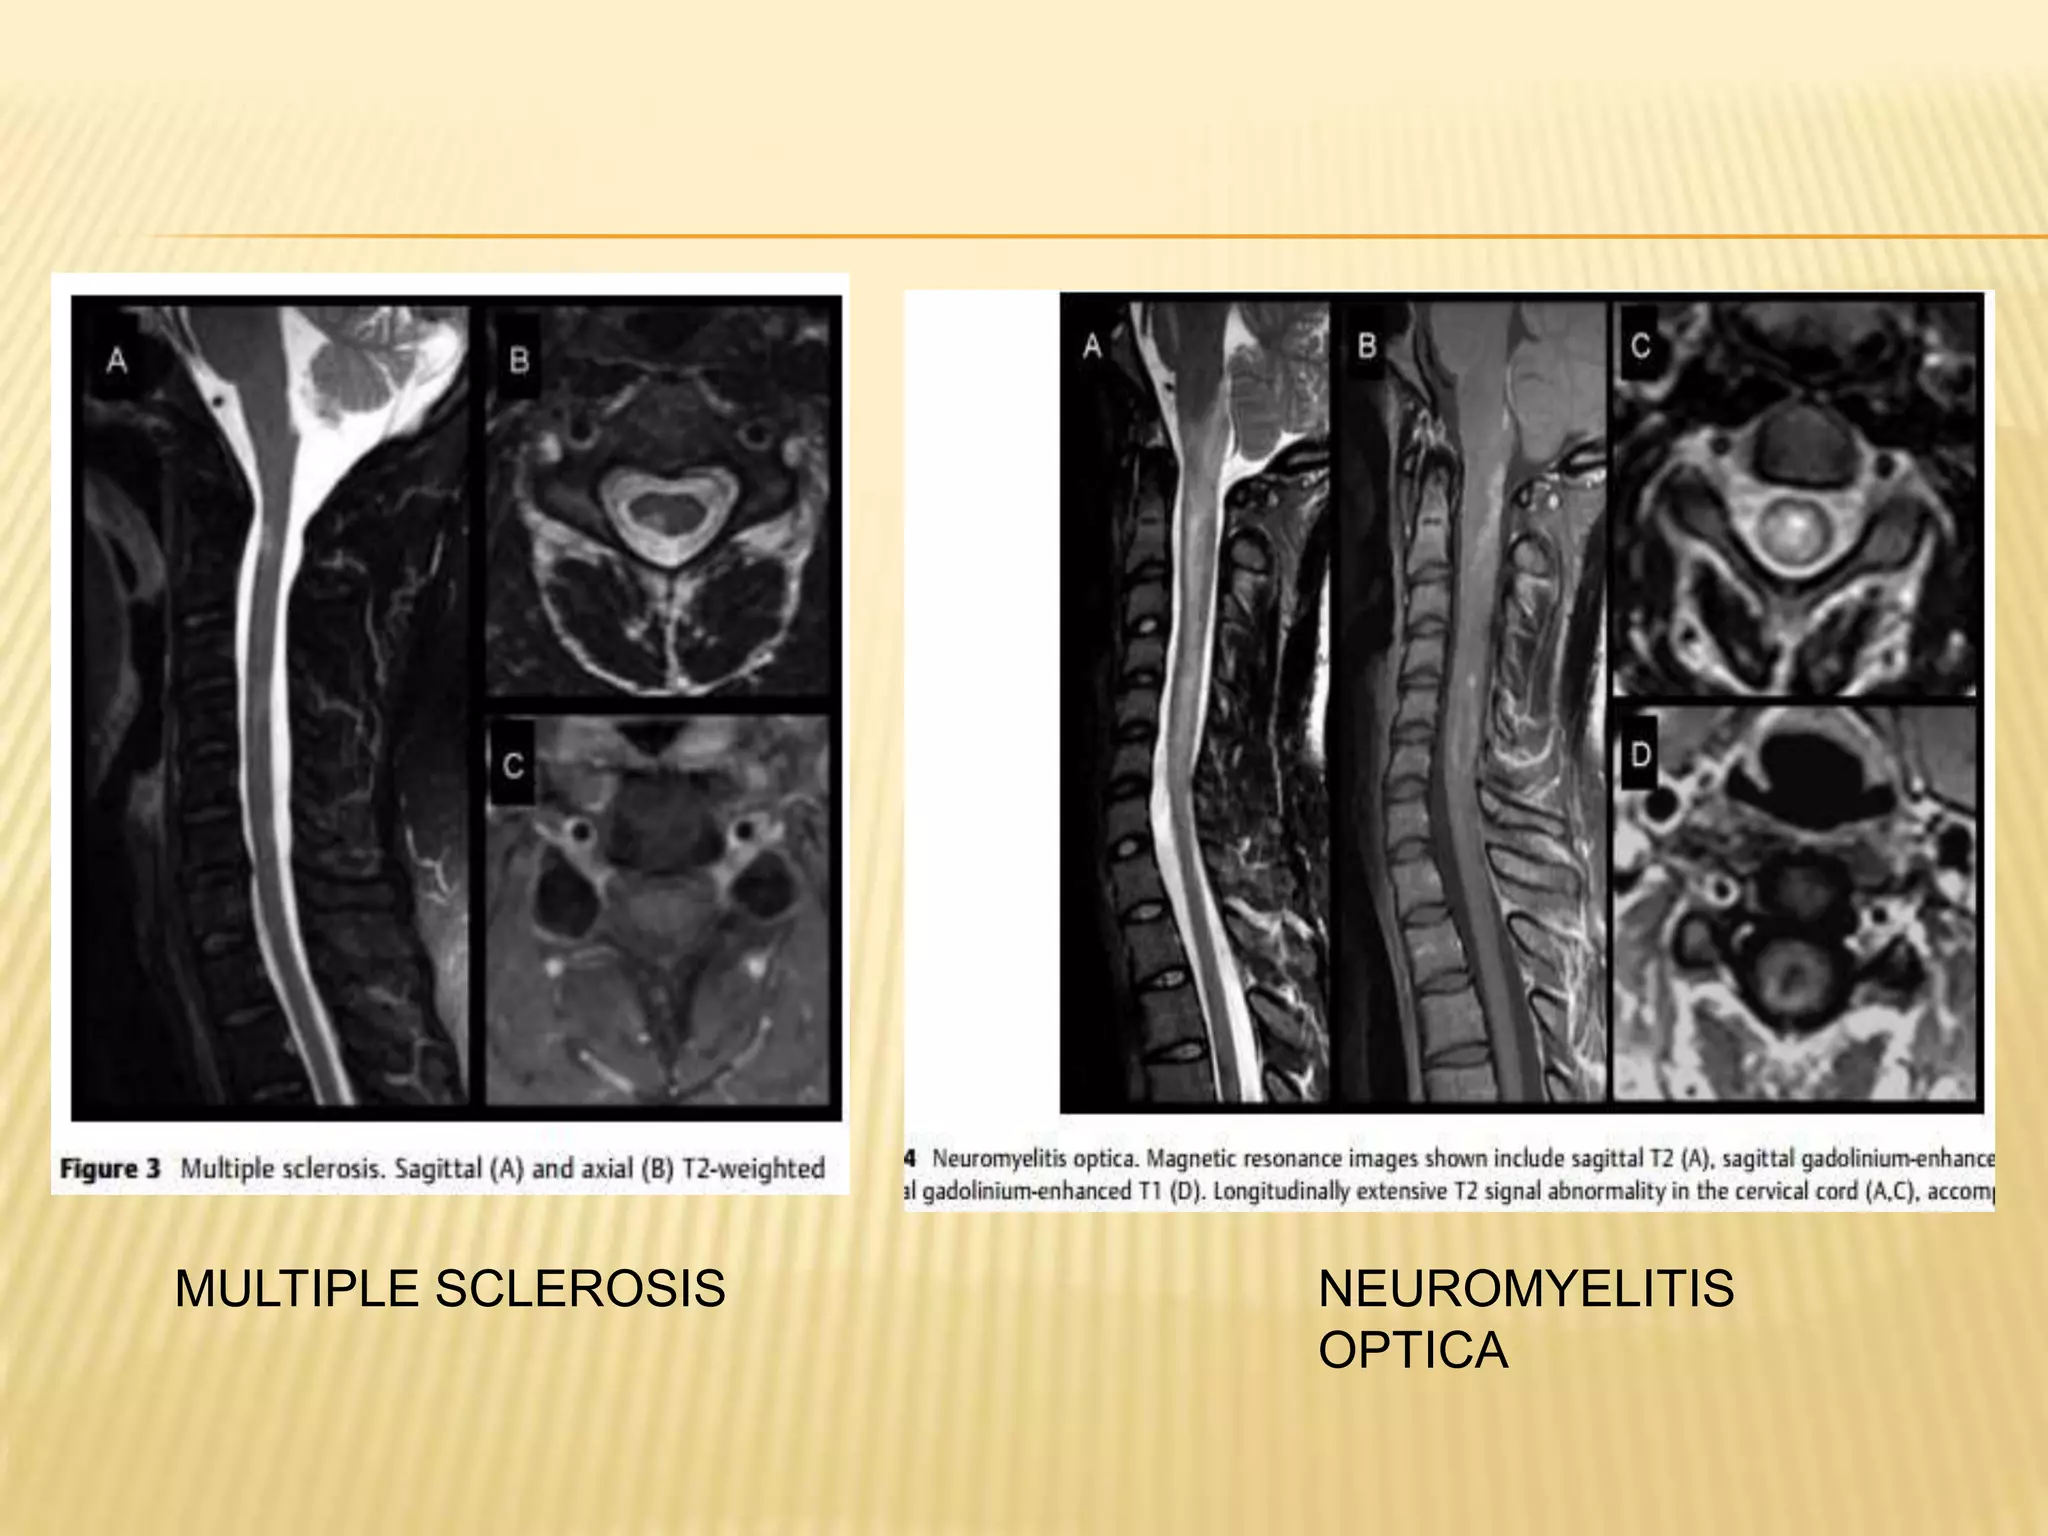

MULTIPLE SCLEROSIS - lesions are

usually small (<2 vertebral segments in

length) and peripheral,

 cause asymmetric symptoms and signs

 Lhermitte sign

 isolated proprioceptive loss of an upper

extremity („„sensory useless hand

syndrome‟‟),

 Brown-Se´quard syndrome, or, more

commonly, incomplete involvement

CSF oligoclonal bands (OCBs) are present in more

than 90% of patients,

other conditions that cause inflammation in the CNS,

including NMO, paraneoplastic disorders, SLE,

neurosarcoidosis, Behçet‟s disease

immunoglobulin (Ig)G index is seen in more than

60%. following equation: IgG Index -(CSF

IgG/albumin)/(serum IgG/albumin). Ratio -0.3 and 0.6

Subclinical optic nerve involvement on visually

evoked response testing

MRI brain FINDINGS predicts relapse

NEUROMYELITIS OPTICA

Lesions are centrally located and necrotic

leading to more symmetric symptoms and

signs,greater disability

 NMO is relatively more common in Asian and

African individuals,

 autoimmune conditions including

SLE, SjoGren‟ssyndrome, and thyroid

autoimmune disorders may coexist

NMO-IgG -recently identified serum

antibody highly specific (>90%) and sensitive

(>70%) for NMO.

 Risk of developing recurrent myelitis or new

onset optic neuritis in patients with an LETM

was more than 50% in NMO-IgG seropositive



MULTIPLE SCLEROSIS

NEUROMYELITIS

OPTICA